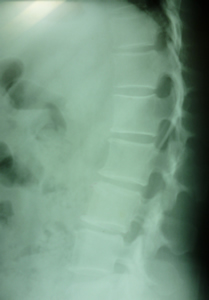

変形性腰椎症

腰椎4番にスベリ症が見られます。

腰椎5番は椎間板の狭窄と過骨化が見られます。

腰椎の変形は年月と共に誰にでも起きることです。

必要以上に心配する事はありません。

治療しながら上手に腰痛と付き合うことです。

腰椎スベリ症(分離症)

腰椎4番がスベリ症です 長い間重量物の運搬と少し猫背が原因でしょうか、

年齢と共に多少のスベリ症患者は多く見受けられます。

過度の腰椎前弯を避けるよう指導し腰筋の柔軟性の腰痛体操を!